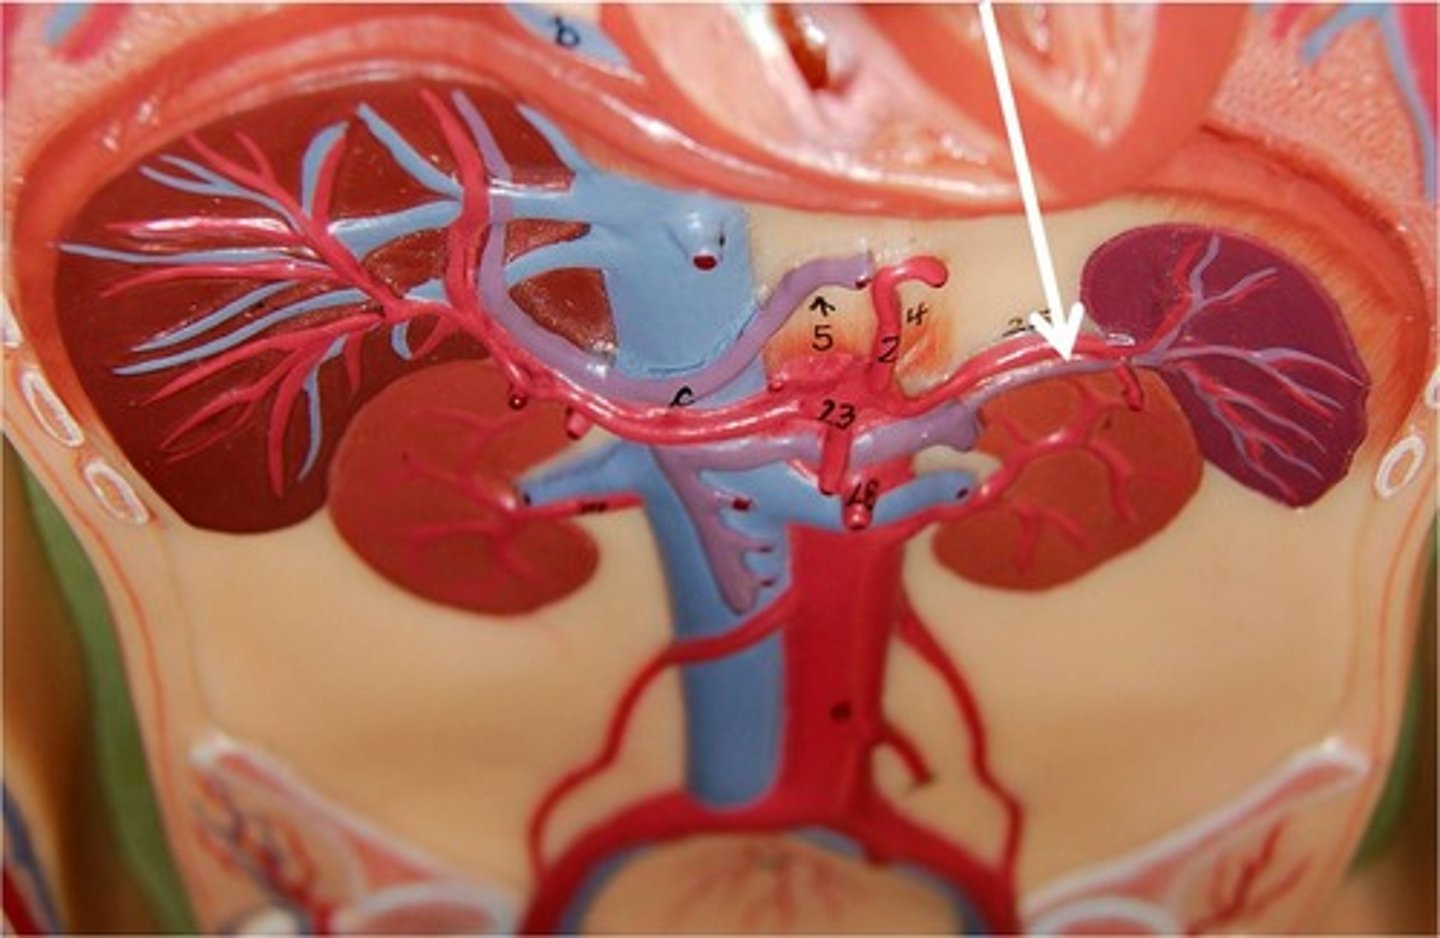

splenic artery

-extends from the celiac trunk to the splenic hilum.

-supplies to the spleen

splenic hilum

site located in the middle of the spleen where blood vessels, lymphatic vessels, and nerves enter or exit the organ.

splenic vein

-Fuses with the superior mesenteric to carry newly filtered blood to the hepatic portal which will bring it to the liver

How would the average age of red blood cells in the splenic artery compare to the average age of red blood cells in the splenic vein?

The average RBC age will decrease because the spleen would have removed many of the oldest RBC's.